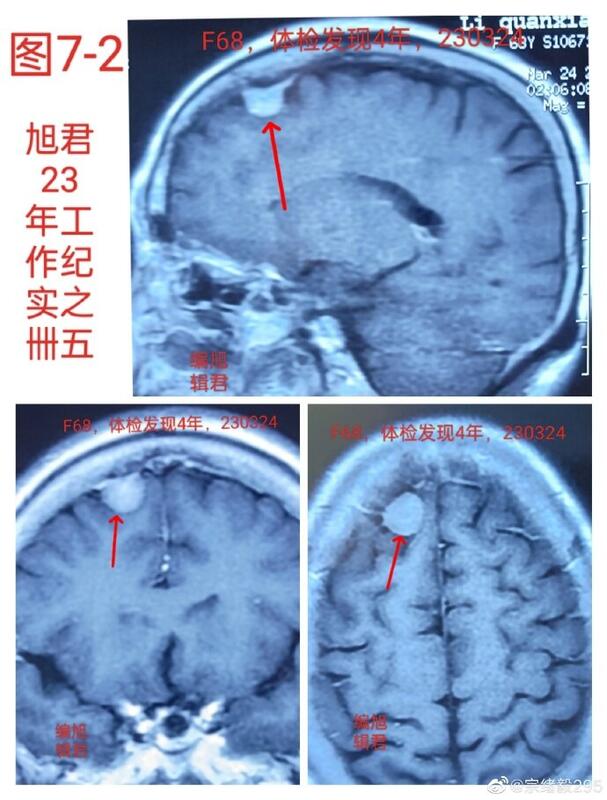

图7,1-2,某患者68岁,体检发现四年,近半年复查无变化,与首次发现报告,亦无变化。

图7-1

图7-2